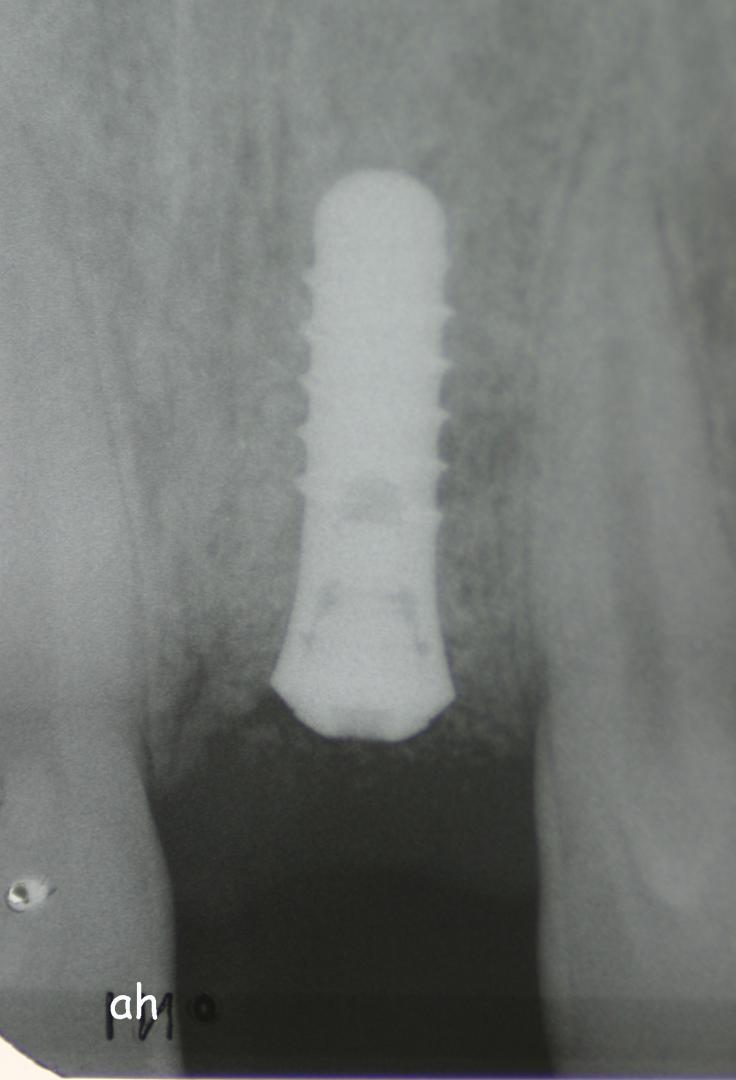

Exemple 7: Un implant au niveau de la deuxième prémolaire inférieure gauche.

Exemple 7: Le moignon vissé sur l'implant.

Exemple 7: La couronne en place

Exemple 7: vue depuis dessus